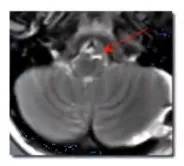

吉娜术前MRI检查结果

1999年,脑干手术究竟能达到何种技术水平?需要认识到,脑干海绵状血管瘤即使在当时世界范围内也鲜有病例报道,更不用说成功手术案例。这种疾病名称中虽包含"瘤"字,但本质上属于血管畸形范畴,是良性病变。这意味着如果能够安全地完全切除,患者有很大机会恢复正常生活。然而这个"如果"背后存在巨大风险——脑干作为生命中枢,手术操作犹如在钢丝上行走,一旦失误将导致严重后果。